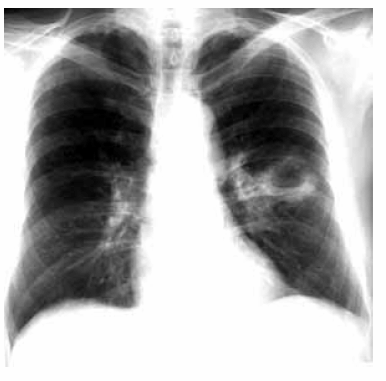

Um homem de 40 anos de idade queixa-se de tosse produtiva, com duração de 14 dias, com grande quantidade de catarro mucopurulento e fétido. Relata que a quantidade de catarro aumentou nos últimos 2 dias e que ele passou a apresentar vários episódios de febre. Informa ser etilista pesado por vários anos e tabagista de 1 maço de cigarros por 25 anos e nega doenças prévias. Antes de procurar o hospital, ele foi a um posto de saúde, há 1 semana, onde foi submetido a exames para tuberculose, que foram negativos, e como não melhorasse, fez uso, por conta própria, de um comprimido de antibiótico (não se lembra do nome), há 1 dia. Ao exame clínico, apresentou sinais vitais normais, péssimas condições de higiene oral e dentária (várias cáries). Ritmo cardíaco regular, sem sopros. ausculta pulmonar, havia redução do murmúrio vesicular no terço médio do hemitórax esquerdo. Exames laboratoriais evidenciaram leucocitose moderada, com contagem diferencial normal, sem outras alterações. O exame radiográfico do tórax na projeção póstero-anterior é apresentado na figura abaixo.